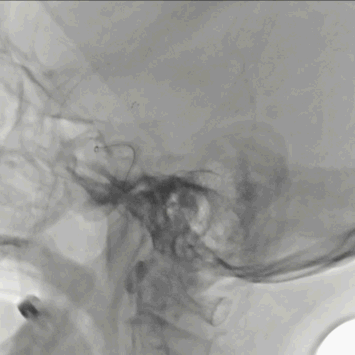

FlowGate 2同轴Catalyst 7、Synchro 2多次调整后穿过C1起始闭塞处,MicroPort Pioneer 2.5mm×20mm球囊C1起始处缓慢扩张,顺球囊Catalyst 7穿过闭塞段,继续向前推进FlowGate 2失败, Catalyst 7 C1抽吸出长条血栓。

Catalyst 7 C1抽吸出大负荷血栓。

Catalyst 7再次通过闭塞处于C2-C4近端抽吸,再无血栓抽出,球囊辅助通过(BTA)技术无法将CAT7带入C4远端,CAT减容任务完成,使用Solitaire FR 6×30支架行完整BADDASS技术, 6×30支架前行张力非常大,释放时并无法顺利推出Rebar 18微导管,导致支架释放略近于预期位置。

支架释放位置不理想,而且前行过程中导致血栓前移,支架并未覆盖血栓头端,经验告诉我们,仅靠软膜支的独立系统可能会通过BGC的血流阻断弥补前向压力(P),远端未覆盖血栓可能会因为血栓之间的粘附力而一并拖出。

充盈FlowGate 2,CAT 7施加张力,希望CAT 7能在支架回撤过程中抓住血栓尾端,但CAT 7在虹吸弯纹丝不动,负压下同时撤出支架与DAC。

BADDASS技术下支架取出长条血栓,3D-DSA可见眼动脉下方重度狭窄,CAT 7在张力下的上行切割狭窄处,导致小夹层产生。

术后RICA造影 :mTICI 3级。